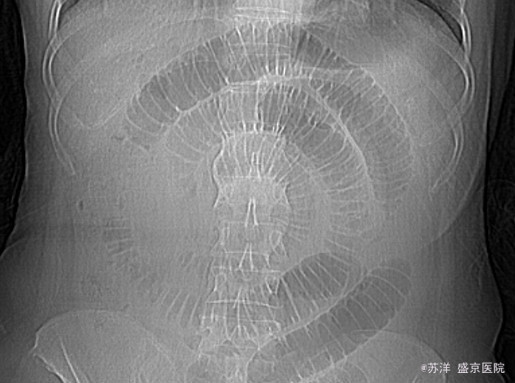

女性59岁,因腹痛60小时来诊,腹痛呈阵发性绞痛,较剧烈,伴呕吐胃内容物,可见胆汁样液。停止排气排便。

腹部饱满,未见肠型,全腹压痛,,无反跳痛及肌紧张,移动性浊音(-),肠鸣音亢进,可闻及气过水声。子宫切除术后10年,腹腔镜胆囊切除术后2个月。 (1)血常规 WBC 12.5×109/L NE% 86.4% (2)肝功能 凝血功能 正常 (3)超声:肝胆脾未见占位病变 (4)CT: 小肠积气积液扩张,低位小肠梗阻;小肠系膜间隙淋巴结增大及渗出;腹盆腔积液. (5)腹部站立正侧位平片:符合肠梗阻表现

初步诊断:肠梗阻 处理方案:结合病史和检查,该患者诊断较为明确,符合肠梗阻。引起注意的是该患者腹部影像检查,可以看到肠管呈花环样螺旋盘绕,给人印象深刻。 这种表现首先考虑存在粘连导致的肠管围绕束带旋转内疝,而且肠管盘绕至这种程度时估测很难自行复位。结合患者血白细胞增高伴腹腔积液,手术指征明确。遂急诊行探查手术,证实为腹腔内粘连束带导致的肠管内疝,肠管活力尚可,予以松解复位,术后恢复良好。